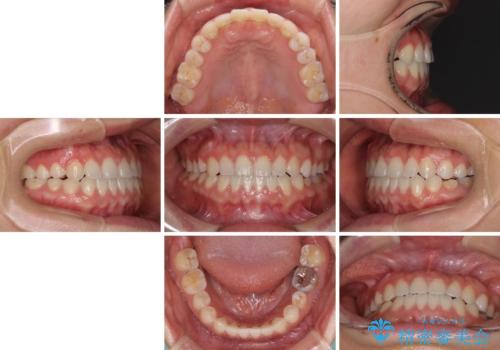

隙間の空いた前歯を治したい インビザライン矯正治療

- 上下の前歯の隙間を気にして来院された患者様です。

インビザラインを用い、上下歯列のスペースを閉じていくこととしました。

治療期間中は奥歯がほとんど咬めない状態が続き、食事に大変苦労されました。

最終的には隙間もしっかりと閉じ、奥歯も咬みやすい状態でしあげることができました。